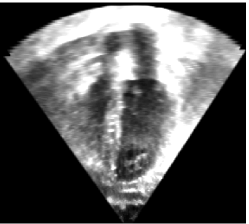

Fig. 9 shows an ultrasound image of the heart (left), an expert segmentation into blood pool, myocardium, and valves (middle) and the intensity distribution for the blood pool and outside the heart (right). These intensity distributions clearly overlap. We initialized the AMF model with this user-defined intensity distribution by sampling from the image followed by kernel-density estimation of the intensities. We re-estimated the intensity-distributions during the optimization. Specifically, given an intensity distribution, we compute the AMF solution, from that we obtain the binarized MAP solution that we use to re-estimate the intensity distributions using kernel-density estimation. We alternate AMF solution and density estimation to convergence. Fig. 9 shows the results of the AMF model for the estimation of label probabilities. The intensity ambiguity is captured in the estimated label probabilities of the AMF model. Regularization behaves as expected: low regularization results in noisy label probability maps. Moderate to high regularization allows capturing of the blood pool (for the MAP solution) while declaring other regions ambiguous or low-probability. Very large regularization declares the full image ambiguous, as expected, because the model will, in this case, prefer overly large segmentation regions.